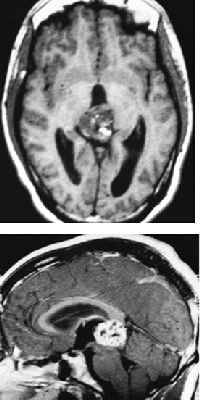

DIAGNOSIS

Magnetic resonance imaging (MRI) is the principal diagnostic test for pineal region tumors. MRI with gadolinium enhancement is mandatory for all pineal tumors to determine the presence of hydrocephalus and to evaluate tumor size, vascularity, and homogeneity. In particular, sagittal MRI reveals the relationship of the tumor to surrounding structures as well as possible ventricular seeding. Computed tomography is complementary but does not provide as much information as MRI. Angiography is not performed unless a vascular anomaly is suspected. Measurement of AFP and b-hCG in serum and CSF is routine in the preoperative workup. If b-hCG or AFP levels are elevated, malignant germ cell elements are present even if histologic examination gives a benign impression, because a small island of these cells in a large tumor may be overlooked. Despite improved imaging and CSF markers, a definite histologic diagnosis cannot be made without pathologic examination of tumor tissue.